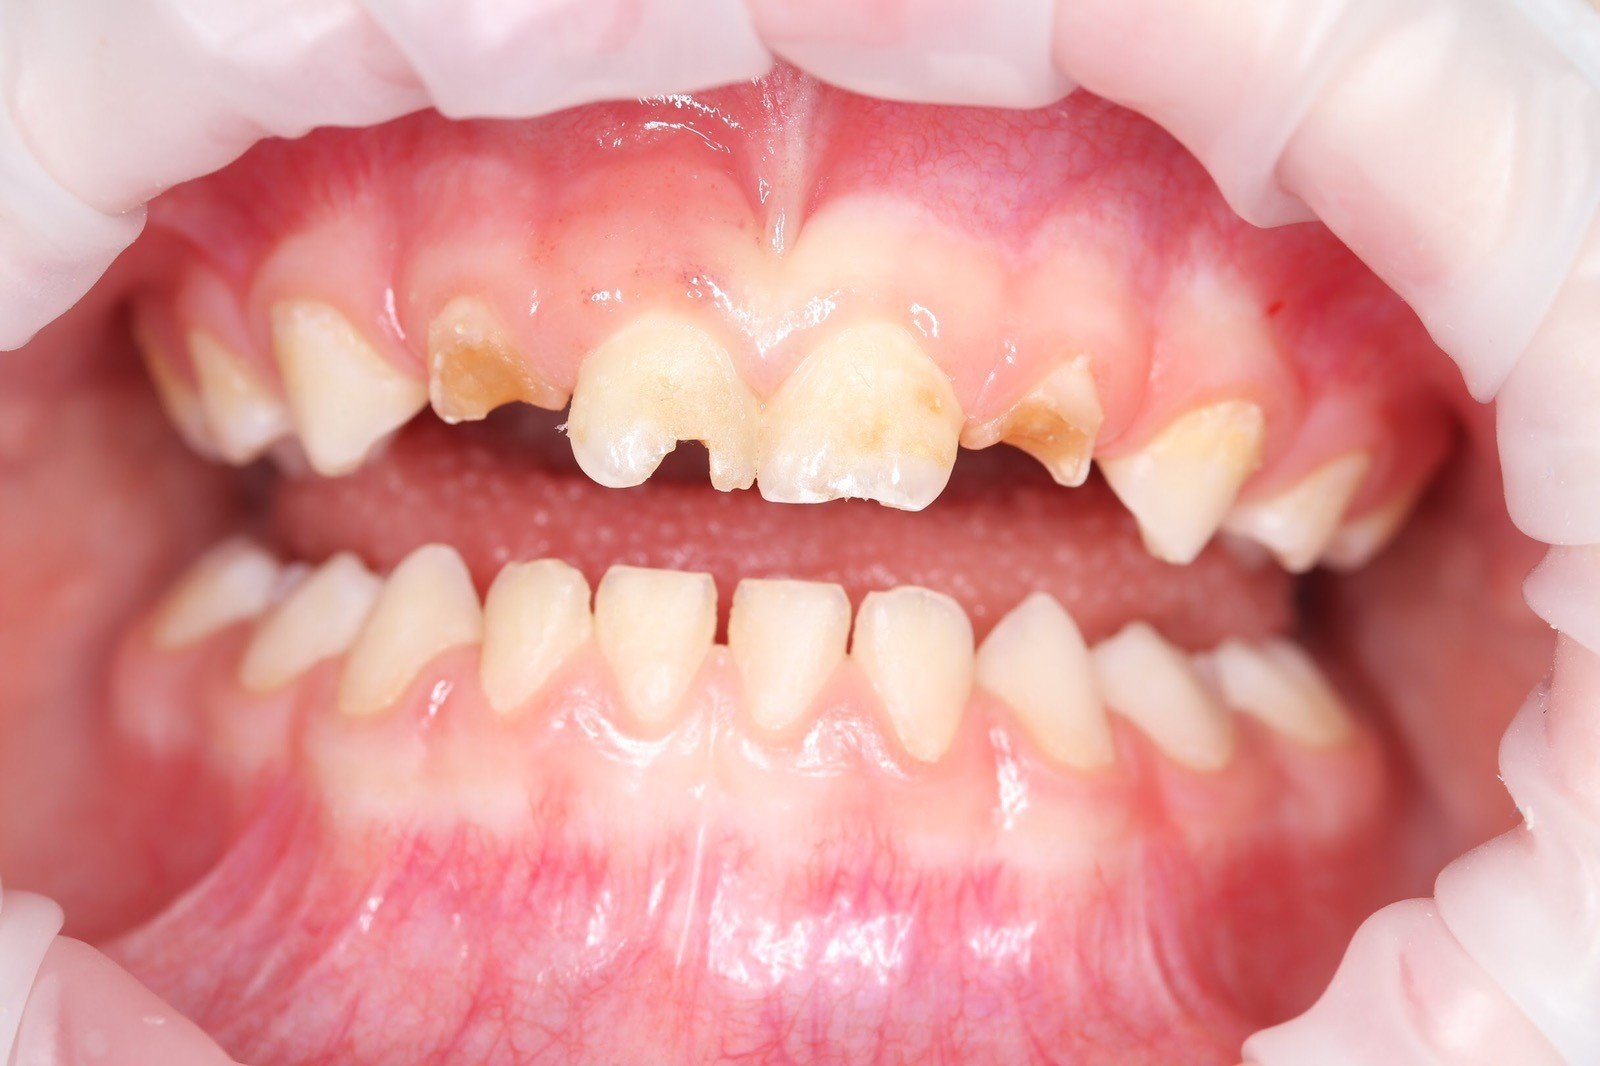

Get the bright white smile you’ve always wanted! Contact us today to get your $139 whitening trays.